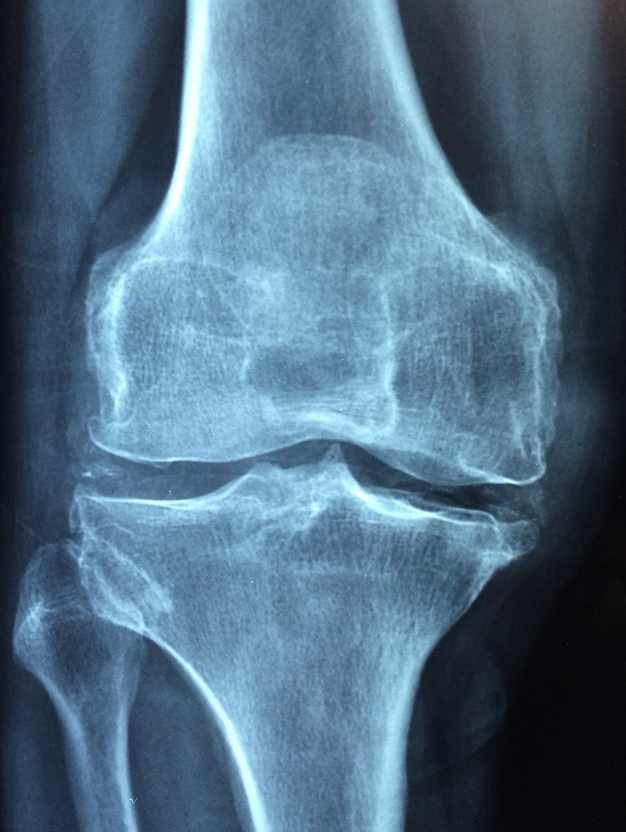

골다공증은 뼈의 밀도가 감소하여 뼈가 약해지고 쉽게 골절될 위험이 증가하는 질환입니다.

특히 고령층과 여성에서 발생 빈도가 높으며, 무증상으로 진행되다가 골절이 발생하는 경우가 많아 예방과 관리가 매우 중요합니다.

골다공증의 주요 증상은 뼈의 약화로 인한 골절이며, 일반적으로 척추, 고관절, 손목 등에서 골절이 발생할 수 있습니다.

골다공증은 골밀도 검사(BMD, Bone Mineral Density)로 진단하며, T-점수가 -2.5 이하일 경우 골다공증으로 진단됩니다.

T-점수가 -1.0에서 -2.5 사이인 경우는 골감소증(골다공증 전단계)으로 분류됩니다.